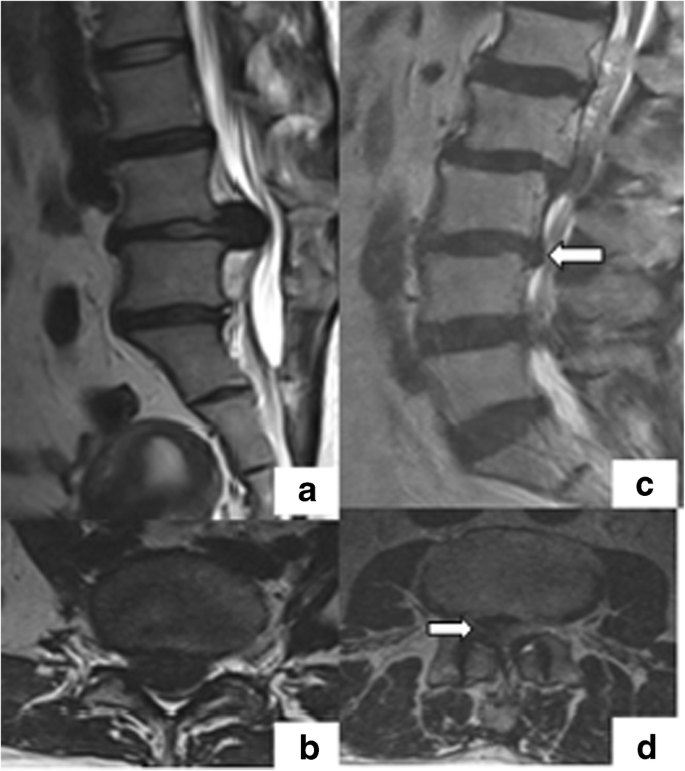

Factors That Influence Neurological Deficit And Recovery In Lumbar Disc Prolapse A Narrative Review Springerlink Breast cancer experts locations & directions research & clinical trials resources.